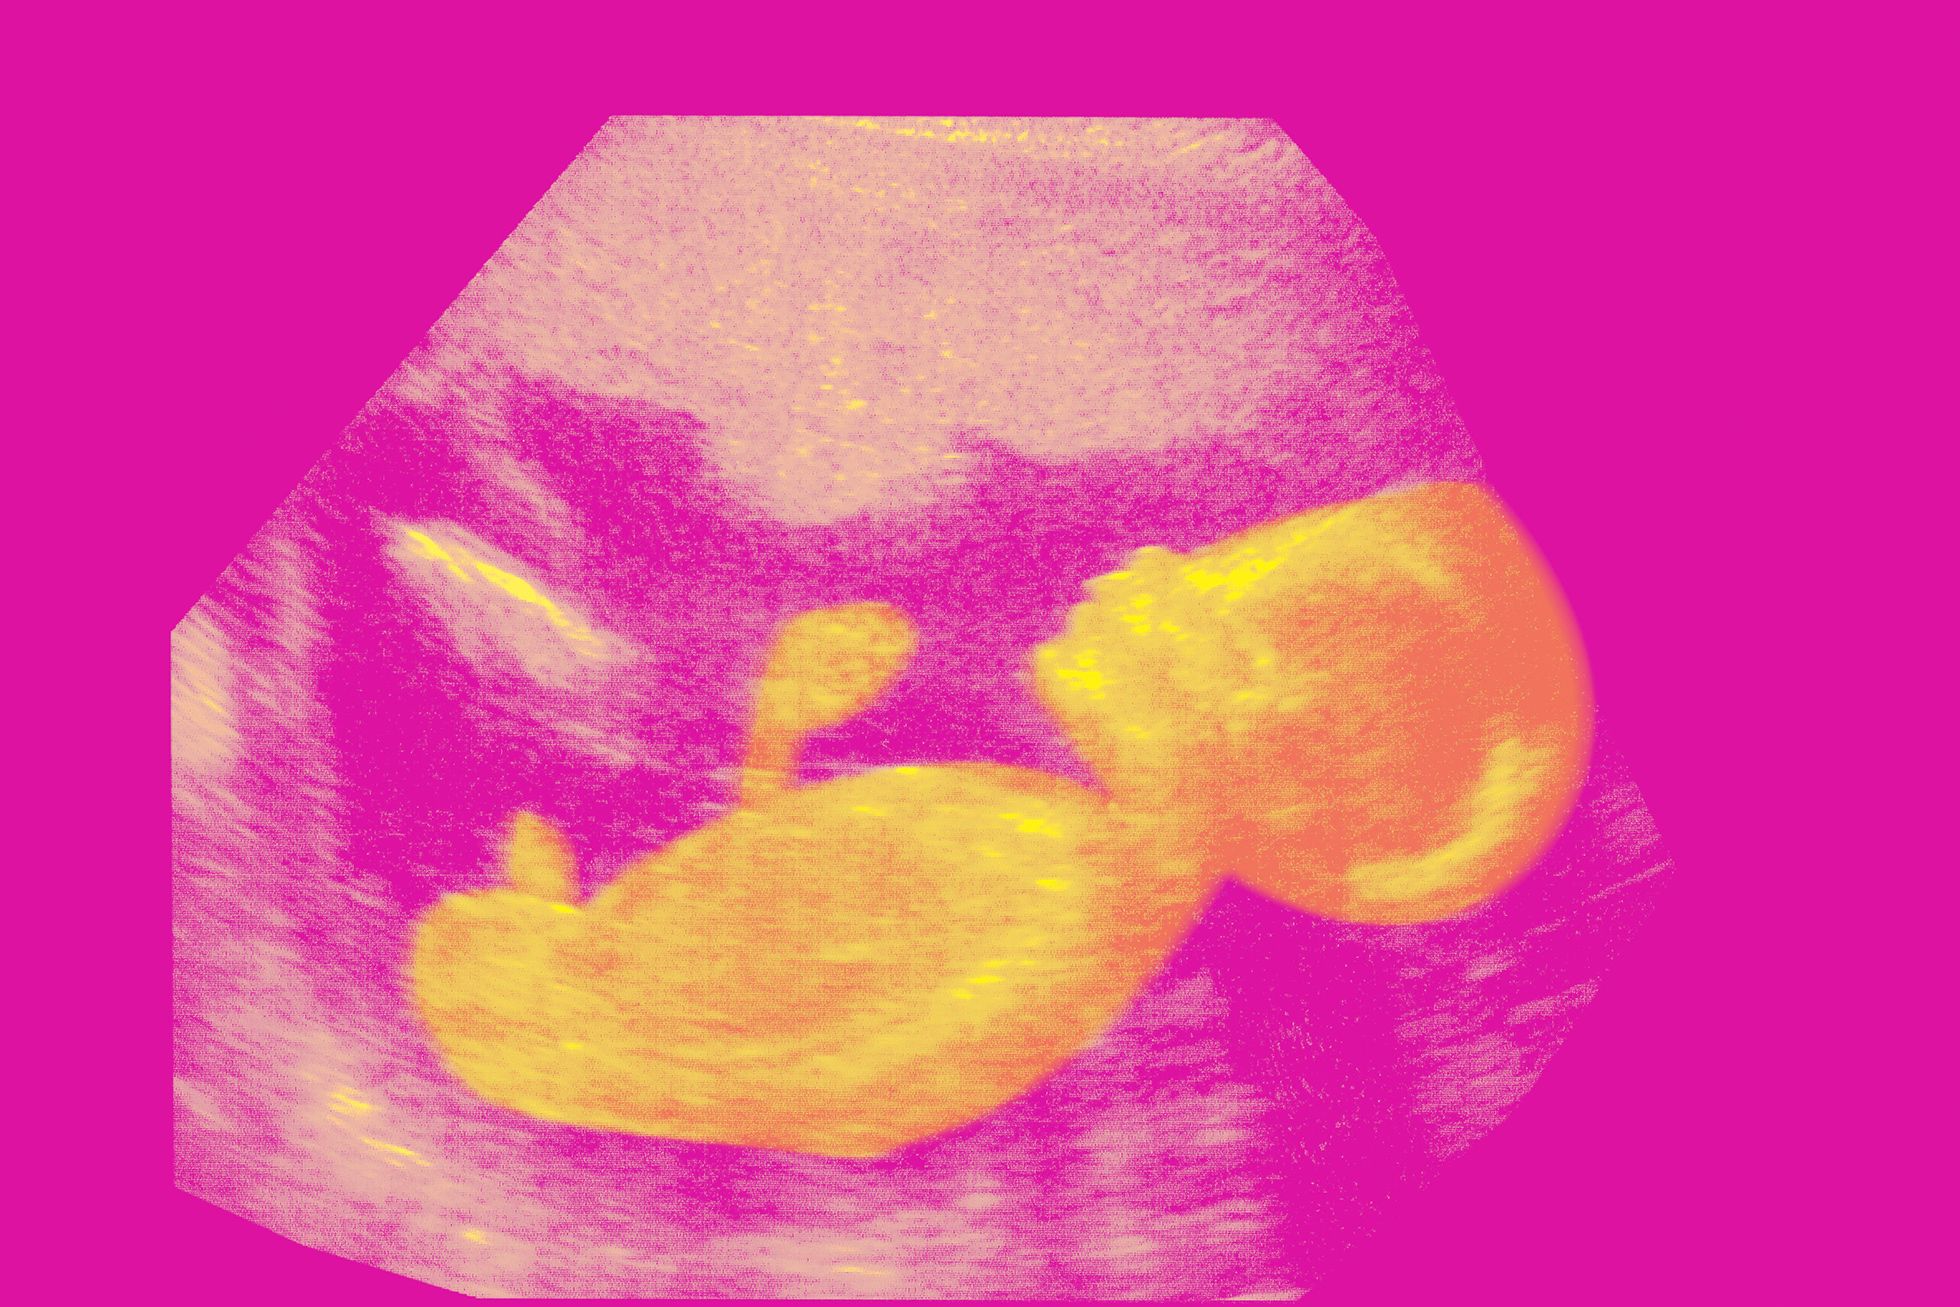

Нужно приготовиться к тому, что и сразу после родов, и долгое время после будет очень много неопределенности. Может шокировать даже то, как выглядит ребенок.

«Люди, которые не видели наших детей, иногда думают, что это трехкилограммовые розовые пупсы, только маленькие», — объясняет анестезиолог-реаниматолог отделения реанимации и интенсивной терапии новорожденных Регионального перинатального центра Калининградской области Элина Сушкевич. В действительности у таких детей очень тонкая нежная кожа, через которую видны сосуды и которая плохо выполняет свои барьерные функции, то есть посредственно защищает от опасных бактерий и вирусов. Подкожного жира у таких детей мало, поэтому они выглядят очень хрупкими и истощенными. У них при рождении отсутствуют некоторые рефлексы, и родившемуся до 35-й недели ребенку сложно координировать сосание и глотание. «Сформированные анатомически системы органов не обладают должными функциональными возможностями и не справляются полноценно с условиями внеутробной жизни», — пишет в ответ на вопрос «Медузы» педиатр клиники «Рассвет» Ольга Евсейчик.